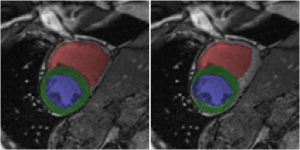

Fig. 3 shows consistent accuracy for the segmentation of all anatomies ({LV,RV,Myo} at {ED,ES}) over a large range of values for . In terms of DSC, Myo is the hardest anatomy to segment, while regarding Hausdorff distance, RV appears to be challenging because of the sensitivity of this distance measure to outliers. These results are around to worse than the best ones in the ACDC challenge [5]. However, no direct comparison can be made with the ACDC challenge results [5] as we did not obtain results on the test set because of the inference approach described in Sec. 2.4 consisting of the assessment of the six central slices per volume.

The bottom row of Fig. 3 shows the segmentation results along with their ground truth for and , where three out of twenty-five cases are misdiagnosed (we show two correct and one incorrect diagnosed case). For the case that has been incorrectly diagnosed in Fig. 3 (rightmost image, ARV misclassified as NOR), the shown under-segmented RV segmentation is representative of the entire ES phase, while for the ED phase, the RV is correctly segmented. Given that ARV relies on RV ejection fraction, such mistake in the segmentation would suggest adequate myocardial contraction and explain why this case is classified as normal. This mistake provides evidence that the features used for training the classification parameters may be strongly correlated with segmentation accuracy. The other two misclassifications involve scans that have imaging artifacts near the heart, similar to the middle image in the bottom row of Fig. 3. Interestingly, the only four cases in the validation set that contain imaging artifacts have a softmax probability (i.e., classification confidence) of around 0.7, while all other scans have a probability near 1. Segmentation performance is unaffected by such artifacts, and two of these four cases are still correctly classified, but it does show that classification performance suffers in scans with imaging artifacts.